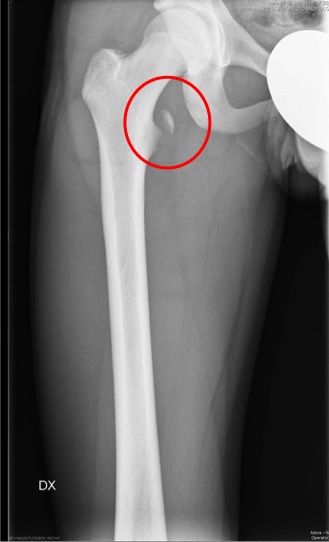

Dopo sette giorni per� Giona ritorna per persistenza del dolore e impossibilit� a sollevare l�arto inferiore; obiettivamente si nota una tumefazione del terzo prossimale del femore con dolore alla palpazione e alla mobilizzazione. Ripetiamo quindi la radiografia, che mette in evidenza un distacco, ma non di una spina iliaca, bens� del piccolo trocantere del femore! (Figure).

I distacchi apofisari sono fratture tipiche dell�et� evolutiva che si verificano quando l�apofisi immatura viene sollecitata da una contrazione muscolare improvvisa e intensa. La sede pi� frequente � il bacino con, in ordine di frequenza, la tuberosit� ischiatica, la spina iliaca antero-inferiore e antero-superiore, e il piccolo trocantere. La clinica � caratterizzata dall�insorgenza improvvisa di dolore inguinale durante l�attivit� sportiva.

Per quanto riguarda la radiografia, va ricordato che questa pu� essere negativa e nei casi dubbi (clinica suggestiva ma Rx negativa) la RMN � dirimente.